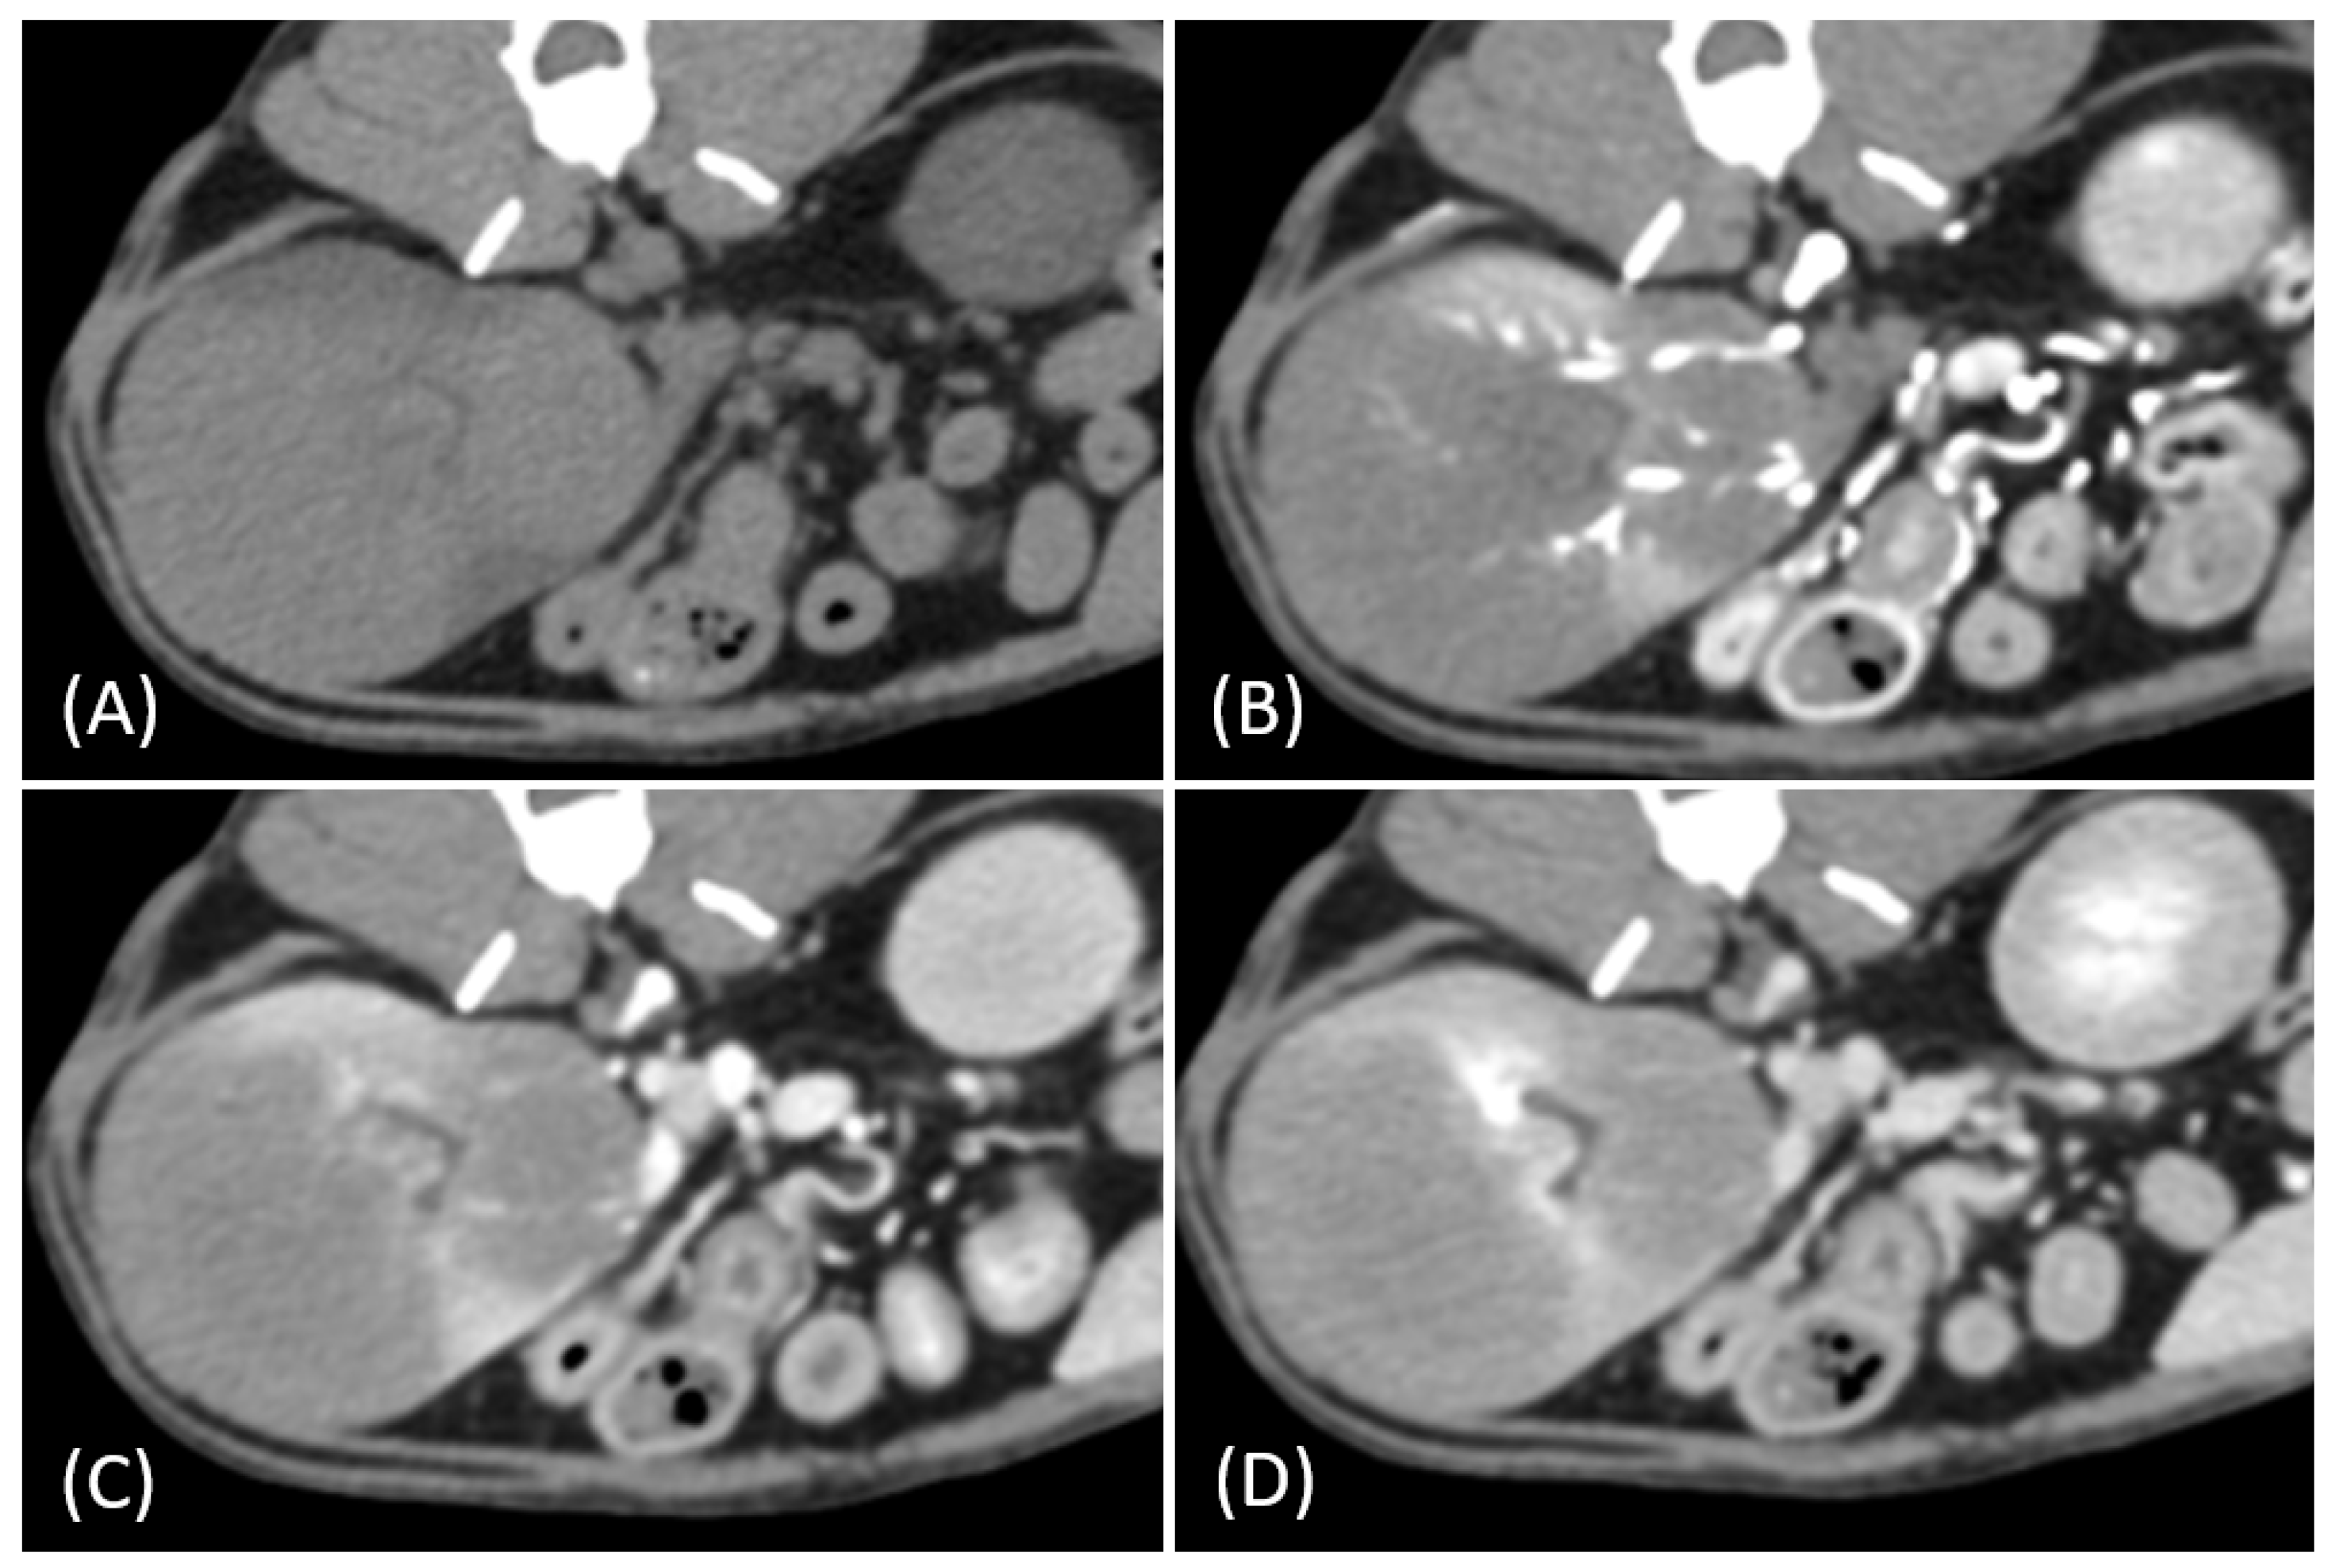

Figure 3.

(A) Pre-contrast, (B) corticomedullary phase, (C) nephrographic phase, and (D) delayed nephrographic/early excretory phase contrast-enhanced computed tomography (CT) images of a cat with bilateral renal and small intestinal lymphoma. The right kidney shows an infiltrative mass (black arrow), while the left kidney has an expansile mass (white arrow). Both tumors are homogeneous and hypodense, demonstrating progressive enhancement.

Tumor growth patterns differed significantly between RCC and lymphoma cases (p = 0.015). RCC predominantly exhibited an expansile growth pattern (11/15, 73.3%) (Figure 1 and Figure 2), while infiltrative patterns were observed in three cases (3/15, 20%) and a combined pattern in one case (1/15, 6.7%). In contrast, lymphomas showed more variable patterns, with infiltrative growth being the most common (5/10, 50%), followed by combined (3/10, 30%) and expansile patterns (2/10, 20%) (Figure 3).

The spatial enhancement pattern differed significantly between the two tumor types (p < 0.001), with RCC typically showing heterogeneous enhancement (13/13, 100%) and lymphomas displaying homogeneous enhancement (9/10, 90%). However, one lymphoma case demonstrated a heterogeneous enhancement pattern (Figure 6A). Tumor vessel enhancement in the corticomedullary phase was observed exclusively in the RCC cases (4/5, 80%) (Figure 1B), while none of the lymphoma cases showed this feature (0/6, 0%) (p = 0.015).